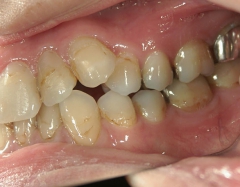

矯正歯科 治療前矯正歯科 治療前

28歳女性 浜松市中区在住

治療期間2年6ヶ月

矯正歯科 治療前 外科手術併用(コルチコトミー)、非抜歯